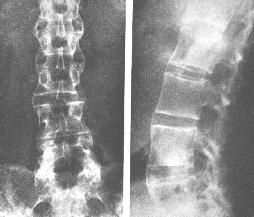

QZ16030094 姓名:陈先生 性别:男 年龄:32岁

- 病情

AS ①晚期 ②重度 病史:5年+

- 治疗

治疗后骶髂关节疼痛消失,腰椎前屈、背伸侧弯活动自如,膝关节无压痛感,复查血沉、C反应蛋白、等各项检查均已达到临床康复的标准。